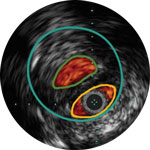

The Pioneer Plus IVUS-guided re-entry catheter is designed to identify true lumen with speed for the most challenging CTOs. With the unique offering of IVUS and a dual-wire system in one device, the Pioneer Plus catheter provides clinicians with IVUS-guided clarity to true lumen re-entry for their patients.

Confirm true lumen or sub-intimal guidewire location

Dr Michael Lichtenberg and Dr Konstantinos Stavroulakis discuss the basics of IVUS image interpretation for PAD intervention. Using case- based examples, they demonstrate the added value of IVUS to assess the architecture and pathology of diseased arteries and how this additional information may influence treatment strategy and improve patient outcomes

Using case based examples, Dr Stavroulakis discusses the four pillars of IVUS, a framework that demonstrates the added value IVUS brings to angiography